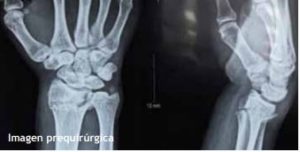

Caso 3.- Masculino de 62 años de edad, con fractura de radio distal y estiloides cubital, se realizó reducción incruenta y fijación percutánea con 2 clavos de Kirschner obteniéndose una adecuada reducción y estabilidad. (fig. 4)